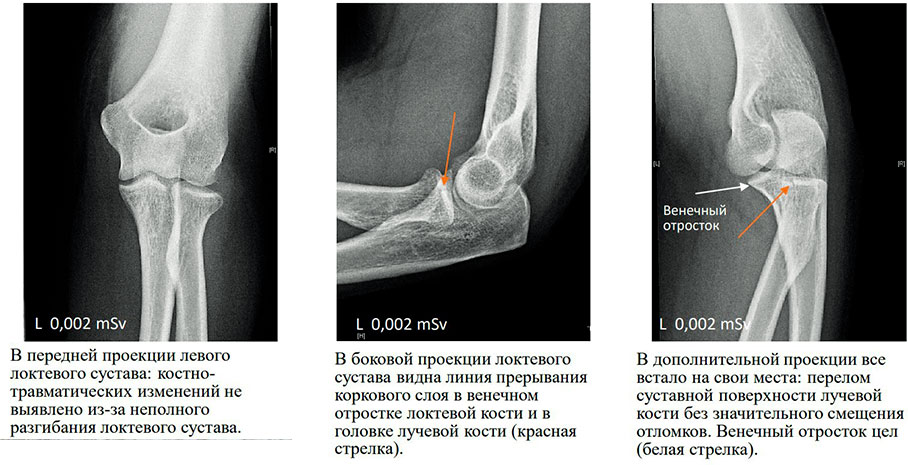

В нашу клинику обратился пациент с жалобами на боль и ограничение подвижности в локтевом суставе 💪🏻 Жалобы возникли около 3-х дней, когда упал на левую руку (поскользнулся в бассейне) во время отдыха. Левая рука в повязке типа «косынка».

По результатам осмотра — область левого локтевого сустава визуально не изменена, умеренный отек и болезненность в верхней трети предплечья, рука полностью не разгибается.

Клинический диагноз: перелом левой лучевой кости в верхней трети.

Рекомендуется: Рентгенография левого лучезапястного сустава.

По ее результатам и установлен точный диагноз, хоть и потребовалось несколько снимков.

Врач-рентгенолог ГК Evolutis Clinic, к.м.н. Плотников Валерий Григорьевич.